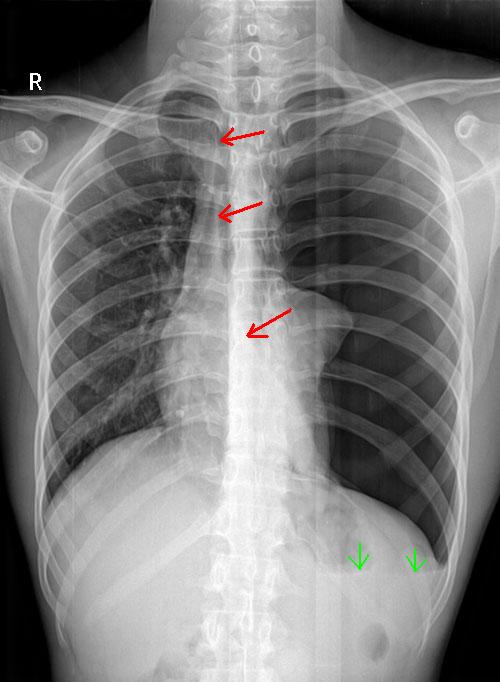

常见者如一侧肺大泡、张力性气胸、局限性阻塞性肺气肿、胸腔积液、肺囊肿和肿瘤等;或一侧肺不张、一侧全肺切除术后。也有因一侧胸腔病变产生瘢痕收缩而将健侧胸腔部分肺脏经纵隔结构薄弱区域牵拉进入患侧胸腔的,如见于肺结核纤维化、慢性胸膜炎瘢痕收缩等。

纵隔疝产生的原因为两侧胸腔的内压不均等,导致压力较高一侧胸腔内部分肺脏经纵隔结构薄弱区突入压力较低的一侧胸腔内,以恢复两侧胸膜腔内压的平衡。